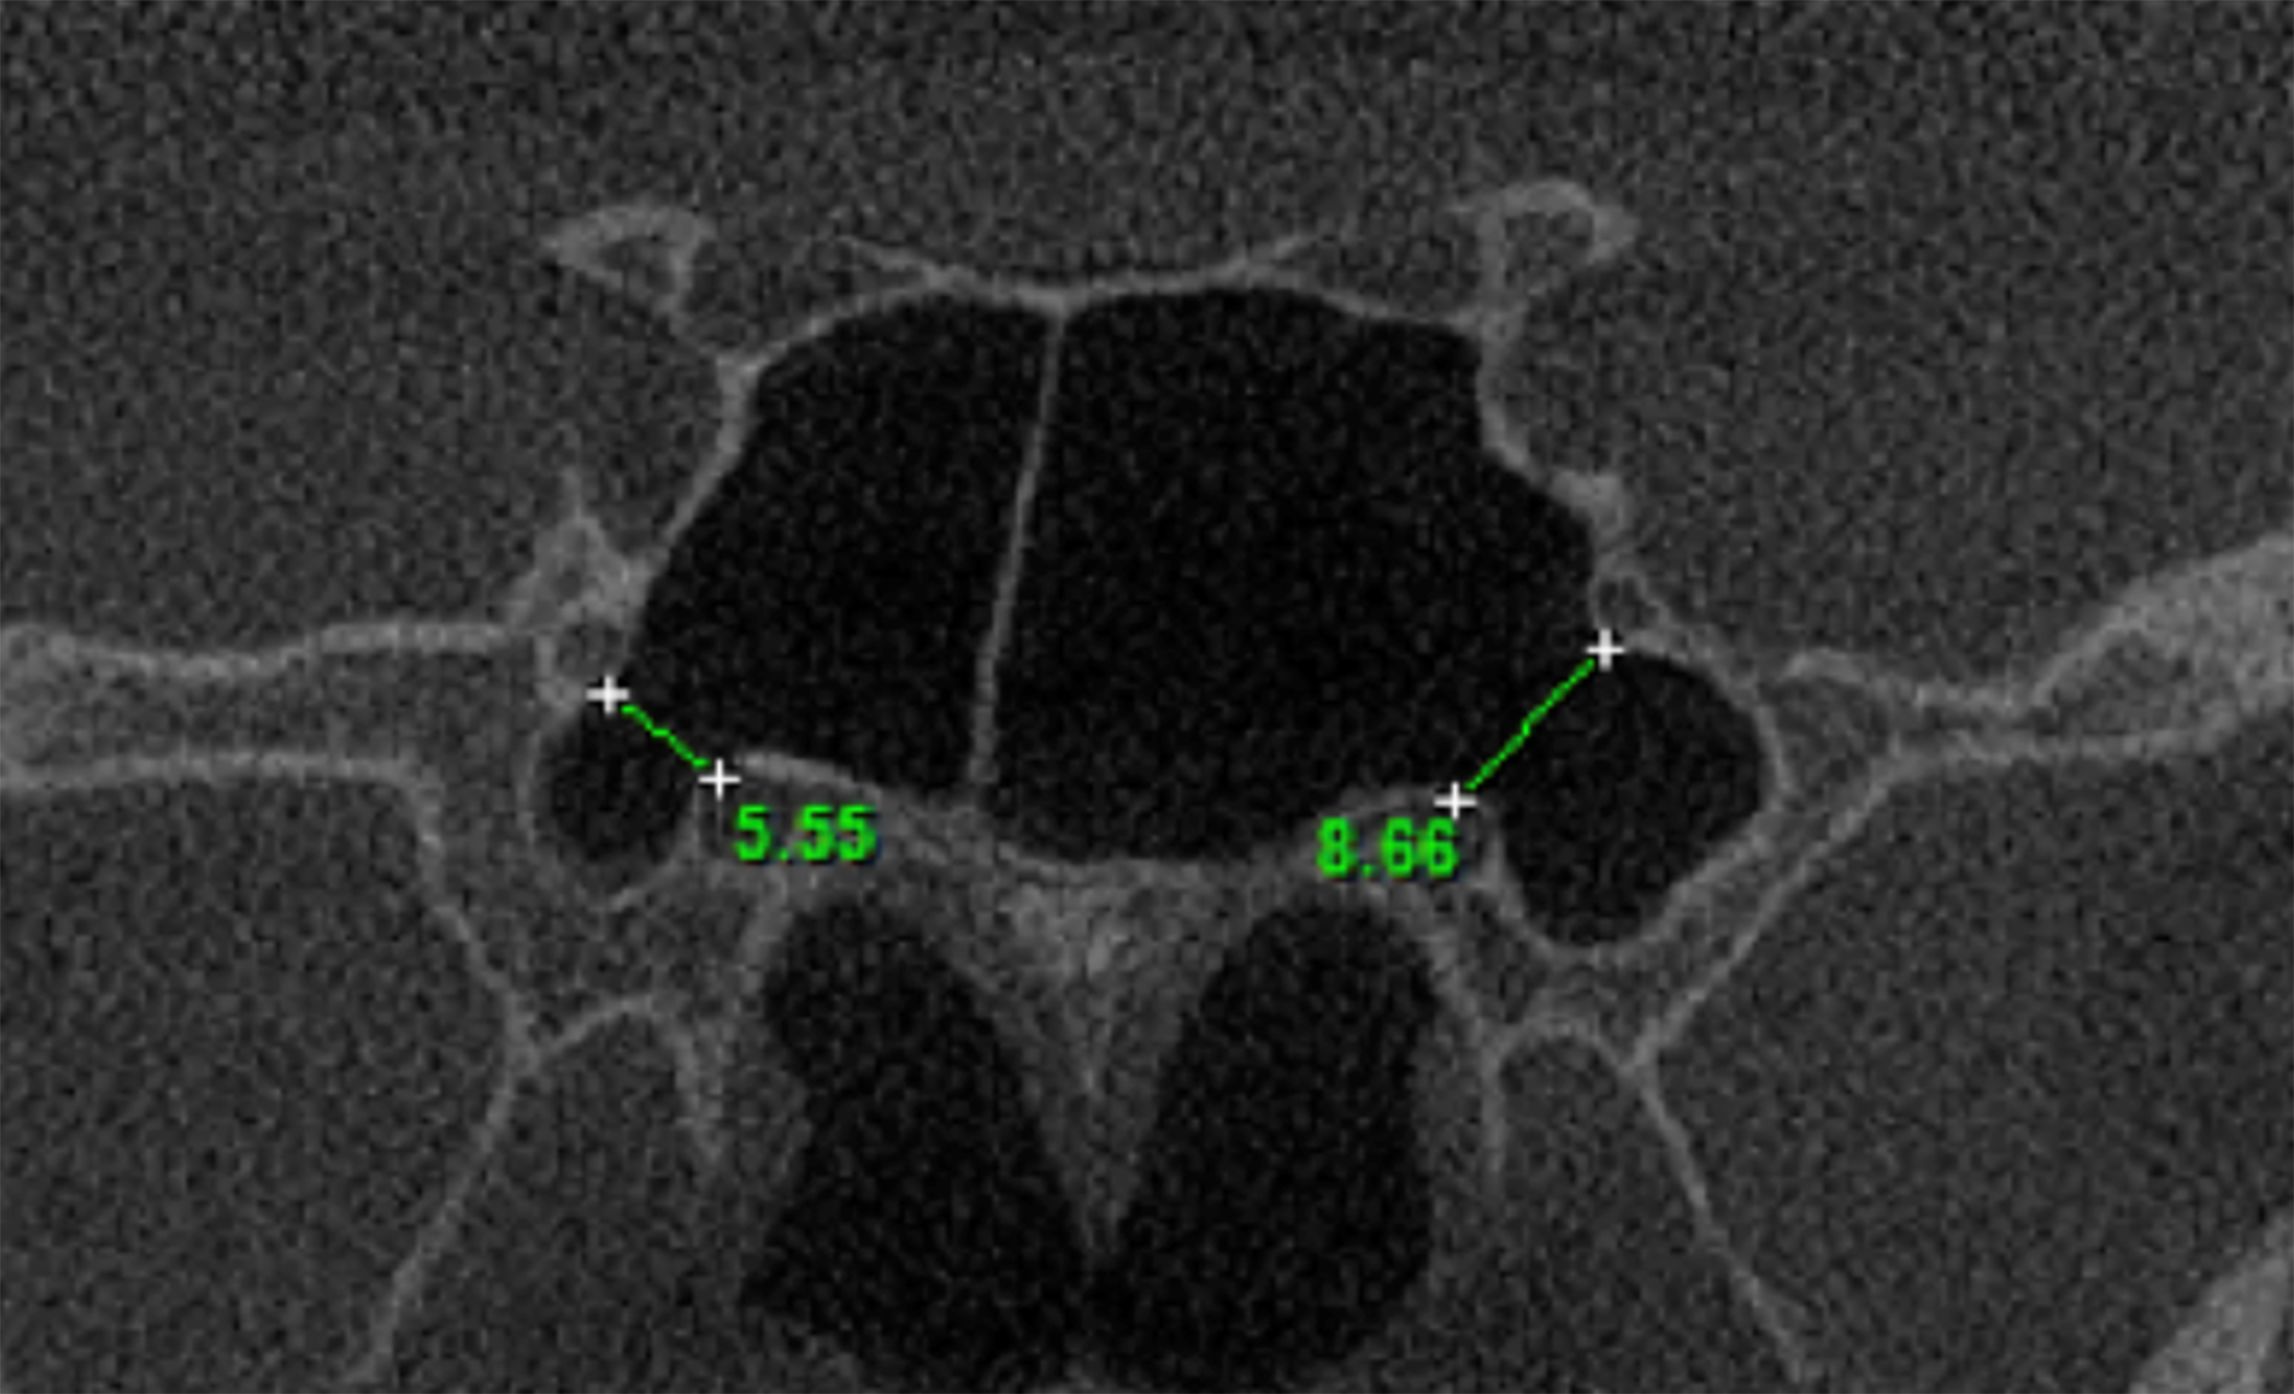

Objective: The aim of this study was to evaluate the pterygoid canal (PC) by Cone Beam Computed Tomography (CBCT), establishing its configuration and proximity with anatomical structures. Material and Methods: We evaluated 398 CBCT exams, all from a public University radiology clinic archive. Four parameters were evaluated: single or double PC, distance between PC and the inferior part of the sphenoid sinus (SS), ratio of PC and SS and the distance between the PC and the foramen rotundum. Results: It was observed that most of the PC of the sample presented simple morphology, the most frequent type of relationship between the PC and the SS on both sides was the close contact with the wall. Among the cases that there were some distances between the PC and the inferior wall of the SS, the mean of this distance did not exceed 3.20 mm, being the left side (3.03 mm) slightly closer than the right (3.20 mm). Finally, the distances between the PC and the corresponding Foramen Rotundum are presented with mean values of 5.87 mm for the right side and 6.31 mm for the left side. Conclusion: CBCT examination is of paramount importance for PC identification; once in the studied sample, the mean values found evidence the close relation between the PC and the SS.